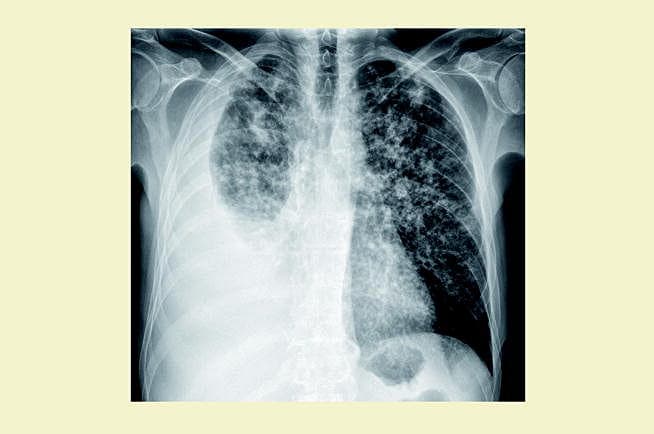

En 49-årig mand med svær morbus Bekhterev (aksial og perifer artritis) diagnosticeret i 2004 blev behandlet med tumornekrosefaktor (TNF)-a-inhibitoren infliximab 500 mg givet intravenøst hver sjette uge samt tablet methotrexat 20 mg ugentligt. Patienten henvendte sig til den 23. infliximab-infusion med klager over åndenød, tør hoste, træthed og vægttab. Han var akut medtaget og hviledyspnøisk med perifer O2-saturation 87%. Stetoskopisk blev der fundet svækket respirationslyd på højre lungefelt. Patientens antireumatiske behandling blev seponeret. Røntgen af thorax viste diffuse nodulære fortætninger i begge lungefelter og højresidig pleuraansamling. Mikroskopi af pleuravæsken viste ingen syrefaste stave, men polymerasekædereaktionsdiagnostik var positiv for Mycobacterium tuberculosis. Endvidere var der positiv plasma-gamma-interferon. Før behandlingsstart med infliximab var der negativt resultat af en Mantouxtest og normale forhold set ved røntgenfotografering af thorax. Patienten kendte ikke sin tuberkulosevaccinationsstatus.